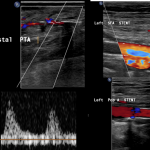

Triphasic flow is seen on Doppler three months later.